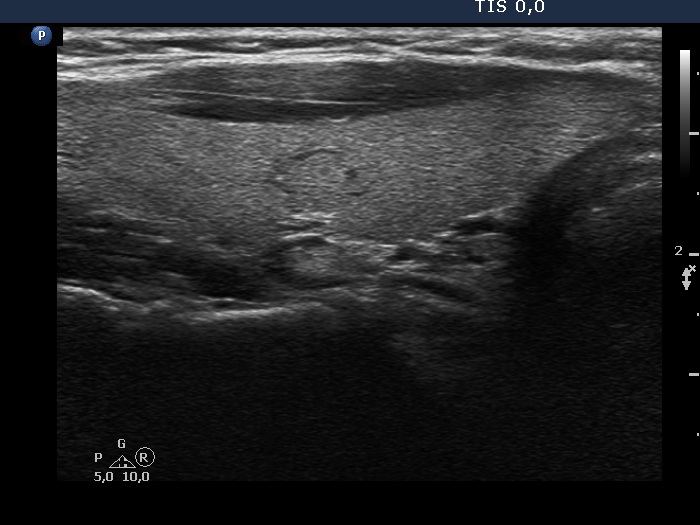

Teamwork - case conp 072 (ultrasonographic picture 2)

Right lobe, longitudinal scan.